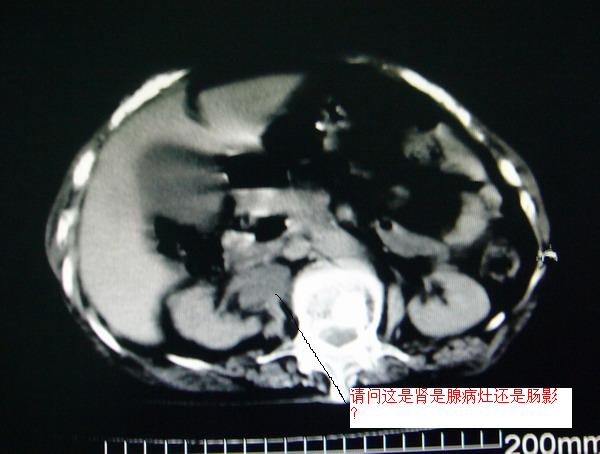

女:83y,转移性右下腹痛2小时,白细胞计数增高。

1.右侧肾盂扩大,肾盏无扩张,考虑:先天性肾盂变异可能性大。

2.胆囊扩张,考虑:胆囊炎。

3.阑尾区域可见以结节样高密度影,结合病史,考虑:阑尾结石,阑尾炎。

右下腹肠系膜增厚,结合病史支持阑尾炎.

右侧壶腹型肾盂可能,建议输路造影或增强

1.右侧肾盂扩大,考虑先天性肾盂变异或肾盂旁囊肿。

2.胆囊扩张,考虑胆囊炎。

3.阑尾区域可见结节样高密度影,结合病史考虑:阑尾结石、阑尾炎。